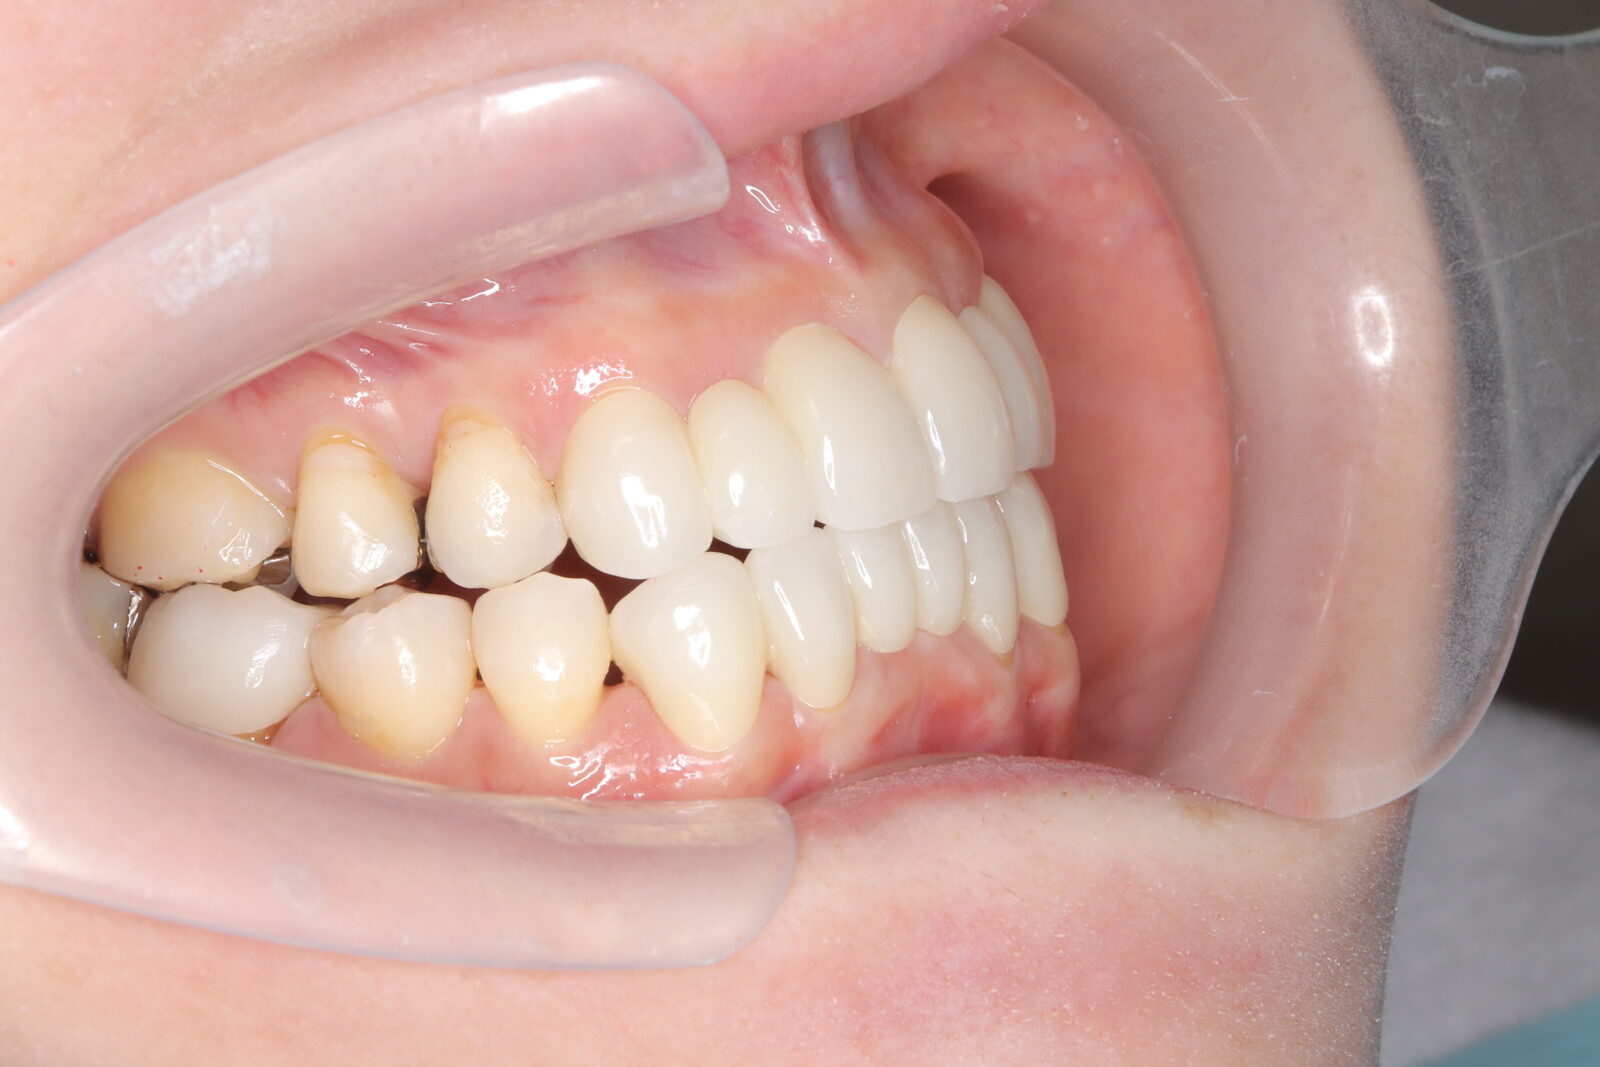

インビザライン(全体矯正)+ホワイトニングコースの症例

上下の前歯の歪みと奥歯のすれ違いをインビザライン(全体矯正)とホワイトニングで綺麗に矯正。

・費用:935,000円(税込)

・治療期間:30ヶ月

・通院回数:30回

・31歳女性

-リスクと副作用-

・長時間マウスピースを装着するため、むし歯や歯周病のリスクがある。治療後はリテーナーを装着しないと後戻りしてしまうリスクがある。

・ホワイトニング剤の影響で知覚過敏が起こる可能性がある。色が徐々に戻る可能性がる。